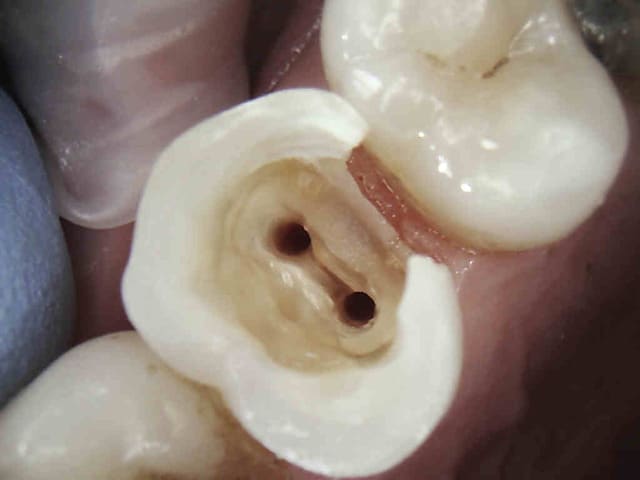

C'est un traitement conforme aux recommandations de la HAS. Celui ci n'est pas conforme : pourquoi ?

Et pourtant obturation à l'apex, thermo-compaction.

Si on parle d'expertise medicale seule, il y a perte de chance par la non mise en place de la digue qui à elle seule entraine la responsabilité du praticien.

+ pas de reconstitution préendo.-)))

Le traitement est bien réalisé, il est sous payé et en plus on pourrait remettre en cause le rôle de l'obturation préendo en NPC.